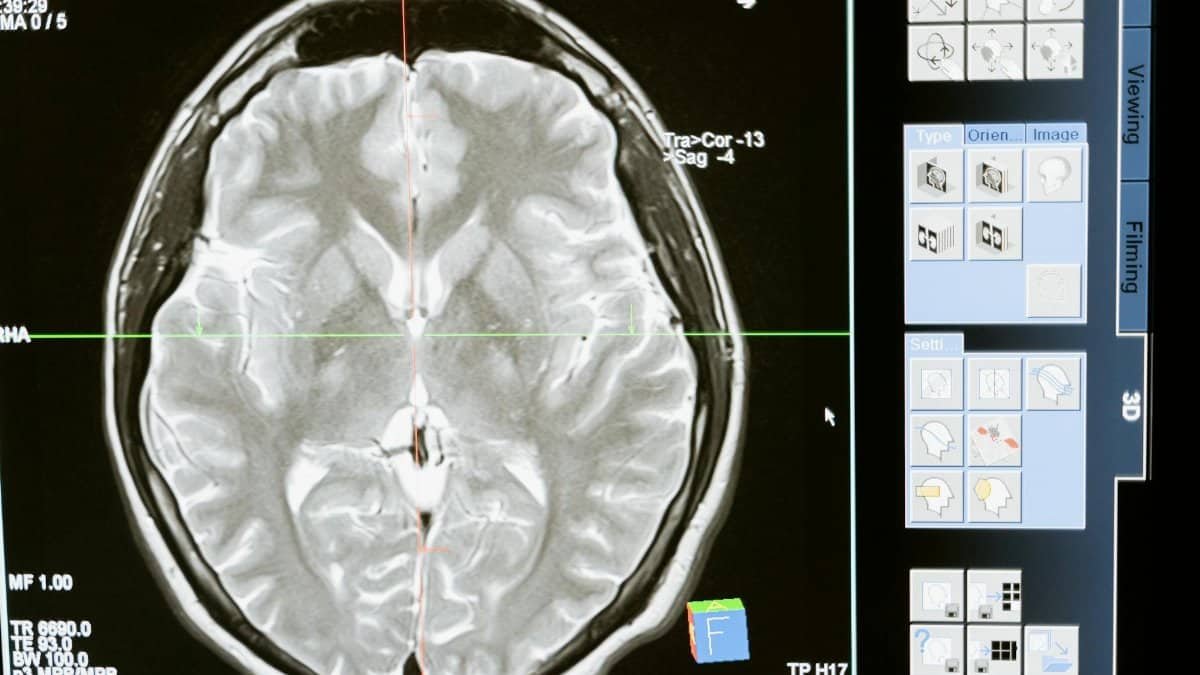

Sleep suffers too. Blue light suppresses melatonin, while mental rumination lingers. A National Institutes of Health overview ties chronic overload to hippocampal shrinkage, mirroring early dementia patterns. Full report accessible via NINDS resources.